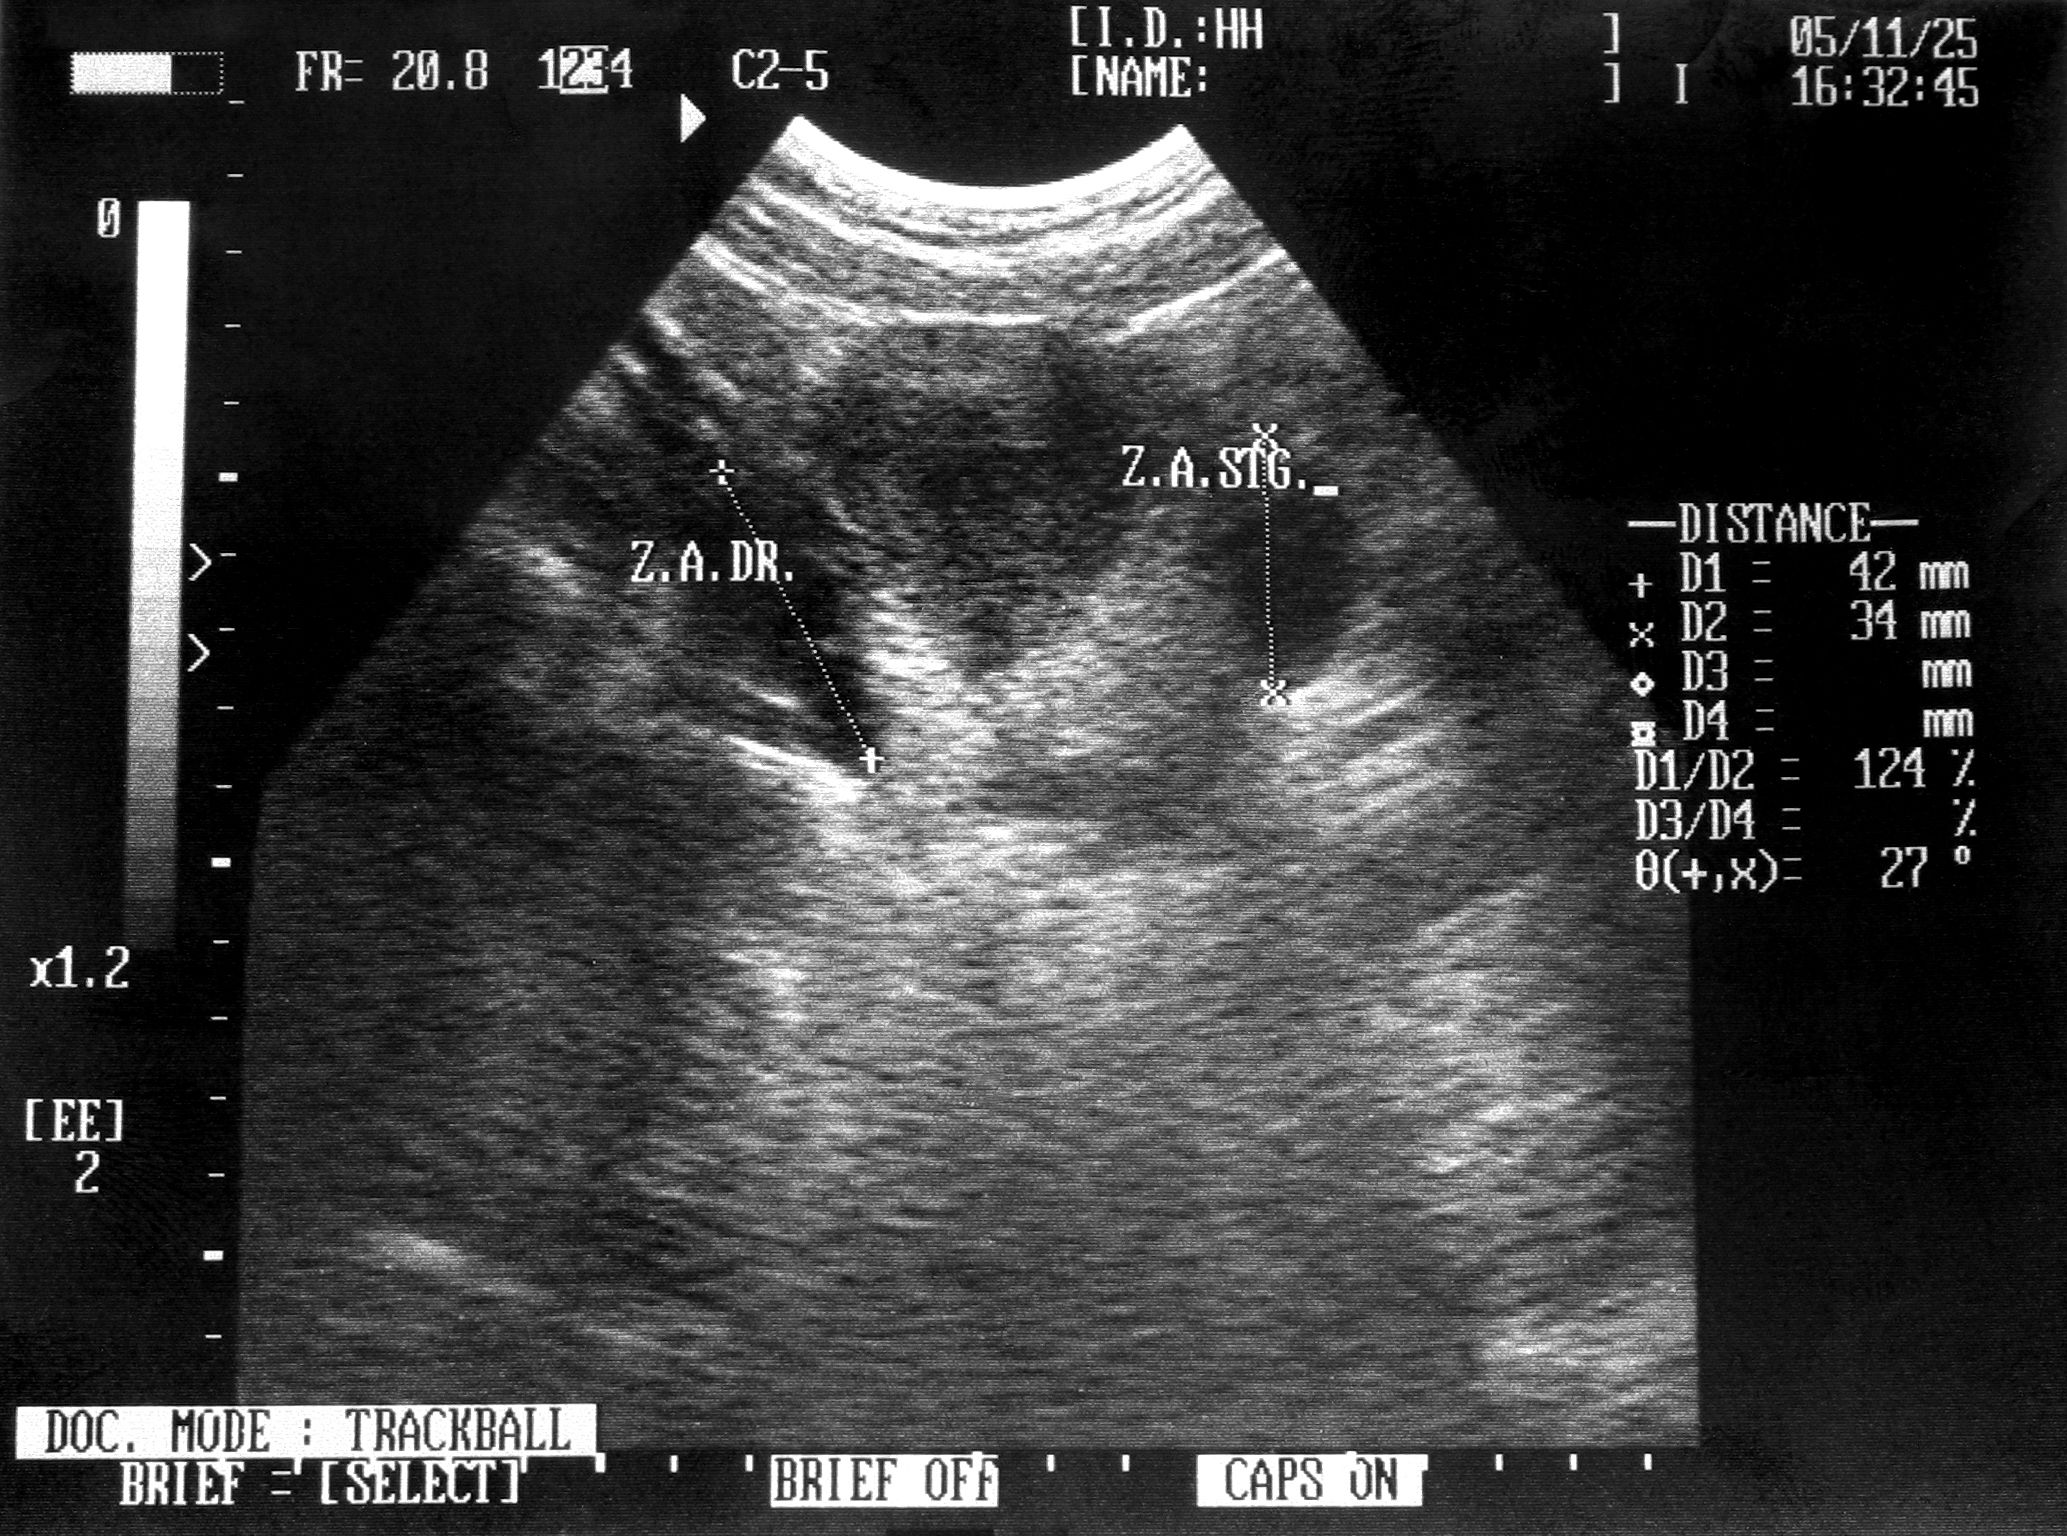

The first trimester screening usually involves a combination of a blood test and an ultrasound. The blood test measures levels of certain substances in the mother's blood, while the ultrasound, often called a nuchal translucency scan, assesses fluid accumulation at the back of the baby's neck. Together, these tests help evaluate the risk of chromosomal abnormalities such as Down syndrome.